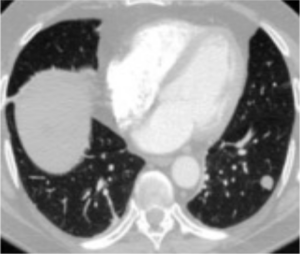

In red: The doctor-annotated area.

In blue: The model's area of attention.

The researchers measure the black area divided by the blue area. In this example, the alignment score would be 25%. When we look at the results, we can see that the alignment scores of the different methods vary greatly: